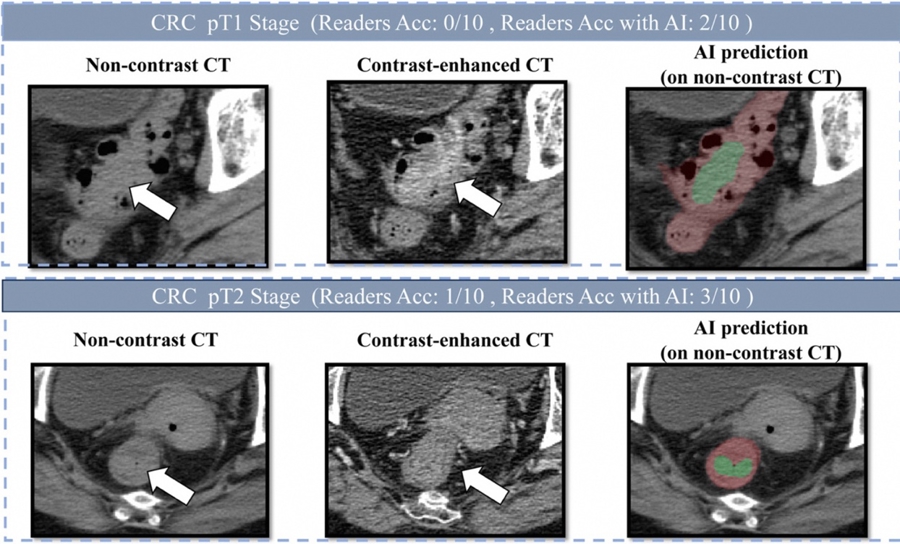

肠癌病灶在平扫CT、增强CT和AI画面上的表现

研究团队发表在欧洲肿瘤内科学会官方期刊《肿瘤学年鉴》(Annals of Oncology,影响因子65.4)上的论文显示,DAMO COCA模型的敏感性(即防止漏诊的能力)达到86.6%,特异性更达到99.8%,即误诊率仅有0.2%。与10名不同年资的影像科医生相比,DAMO COCA模型的敏感性显著高出20.4%,在乙状结肠、直肠等易漏部位上的表现尤为突出。而在AI辅助下,医生的敏感性和特异性可分别提高14.5%和3.1%,有效减少临床漏诊。